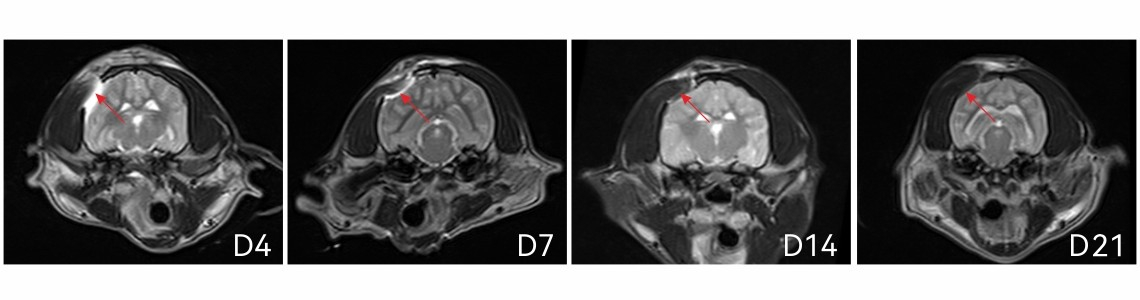

MRI demonstrated complete degradation of Immiseal™ in canine brain.

Implanted material was visible at day 4, 7, 14 and mostly invisible by day 21.